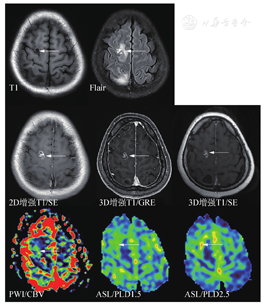

最低标准中,核心是强调了薄层扫描。3D是各向同性块扫描,重建后的单层图像可达到1mm或者0.6mm薄层厚度。共识建议3D扫描,如果不能进行3D扫描,2D扫描层厚要求是3mm;在序列选择方面,首选SE序列。SE是经典MRI序列,病灶显示度高,但扫描时间略长。如果不能进行增强后3DSE序列扫描而使用了3DGRE序列扫描(优点是快,缺点是由于白质信号增高而导致病灶对比度不够,皮质浅表病灶显示差,由于不能附加压脂导致颅骨转移瘤显示差,以及亮血效应带来的脑沟内血管过度显示),建议增加一个增强后2DSE序列。各序列实例比较见图2。

另外,DWI由于非常有诊断价值和扫描时间短,建议始终放在平扫序列里。而注射造影剂前的平扫中,只扫Flair序列,T2放在增强后扫描。优化标准中,主要增加了DSC灌注扫描(可能对鉴别肿瘤复发和放射性坏死有用)、增强后Flair(显示软脑膜转移病变较常规增强T1MRI效果好)以及增强后长时间延迟扫描(60~105 min,以期显示小病灶)。关于增强后Flair序列,对于脑膜转移的增强显示能力已被认可。对于脑实质内的转移瘤病灶,并不能增加诊断信息,但是对于靠近皮质的表浅病灶,显示能力超过常规增强T1,详见图3、图4。不同MR扫描机的序列名称不同,但序列的本质一致。